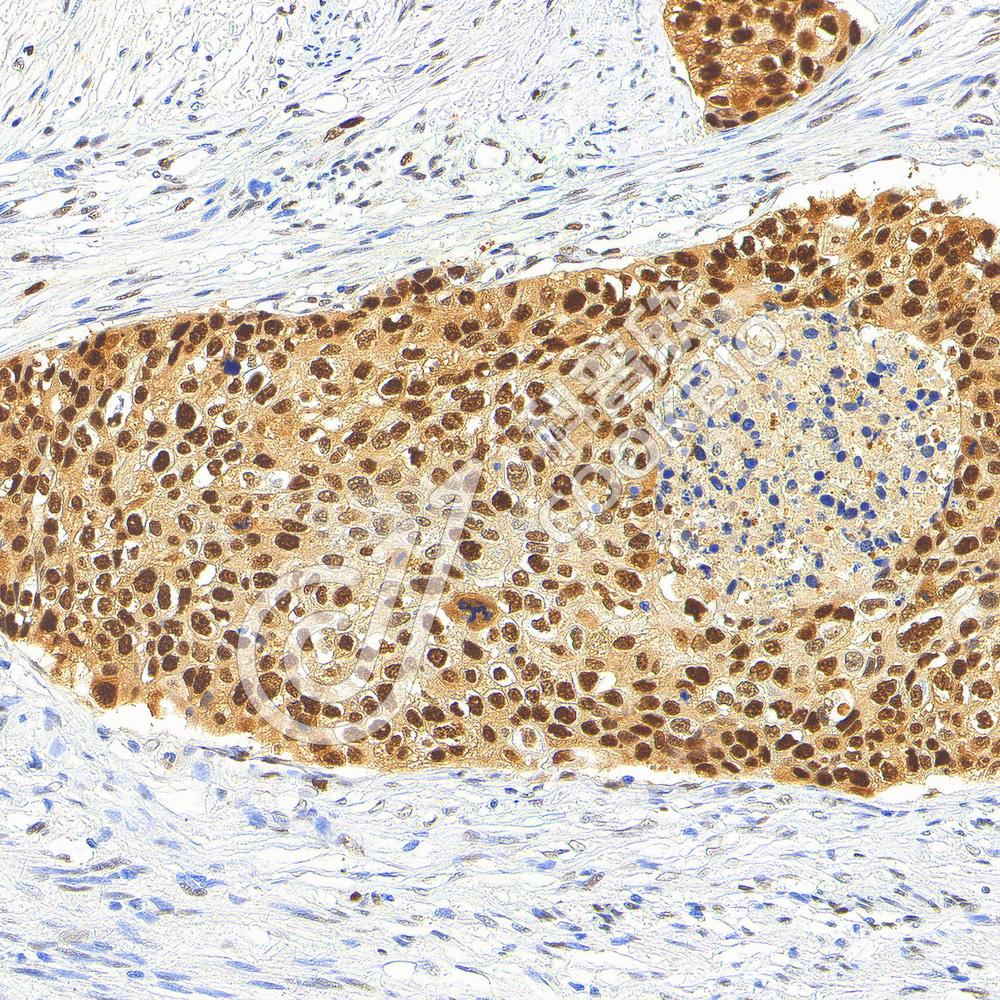

IHC检测PCNA蛋白(货号 K545030).

样品: 人食管癌, 4%多聚甲醛 (货号KSG1101) 固定12-24小时.

抗原修复: Tris-EDTA抗原修复液(pH 9.0) (KSG1203), 98℃, 20分钟.

—抗: 1: 900稀释, 4℃ 孵育过夜.

二抗: S-vision免疫组化多聚二抗(山羊抗小鼠), 即用型(货号KB3903), 室温孵育20分钟.